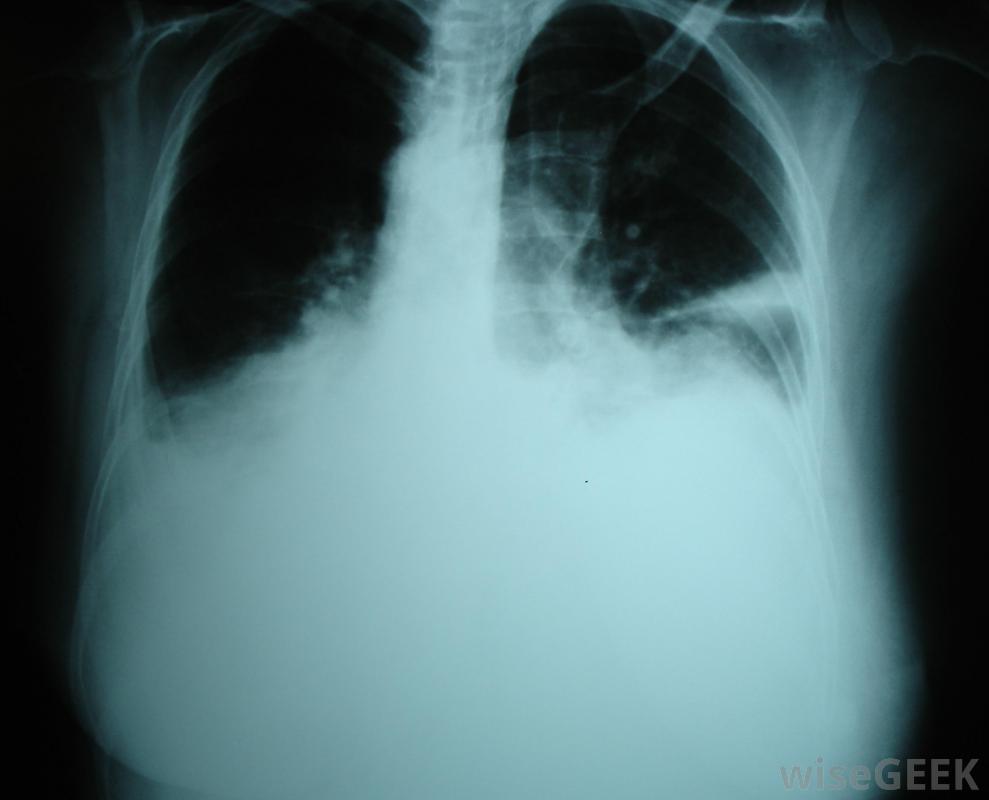

胸腔积液可能是fontan手术的并发症。

Fontan手术通常在婴儿两岁后进行,因为婴儿由于血管阻力高或血液通过循环系统需要大量的工作而无法忍受手术。并发症可能包括感染、胸腔积液或积液肺部和心房颤动。这些并发症可能需要短期或长期使用药物、胸腔导管和手术。在某些情况下,Fontan手术可能无法充分改善患者的健康和生活质量,患者可能需要心脏移植。然而,对于许多患者来说,手术使孩子能够正常发育,过上正常、健康的生活。